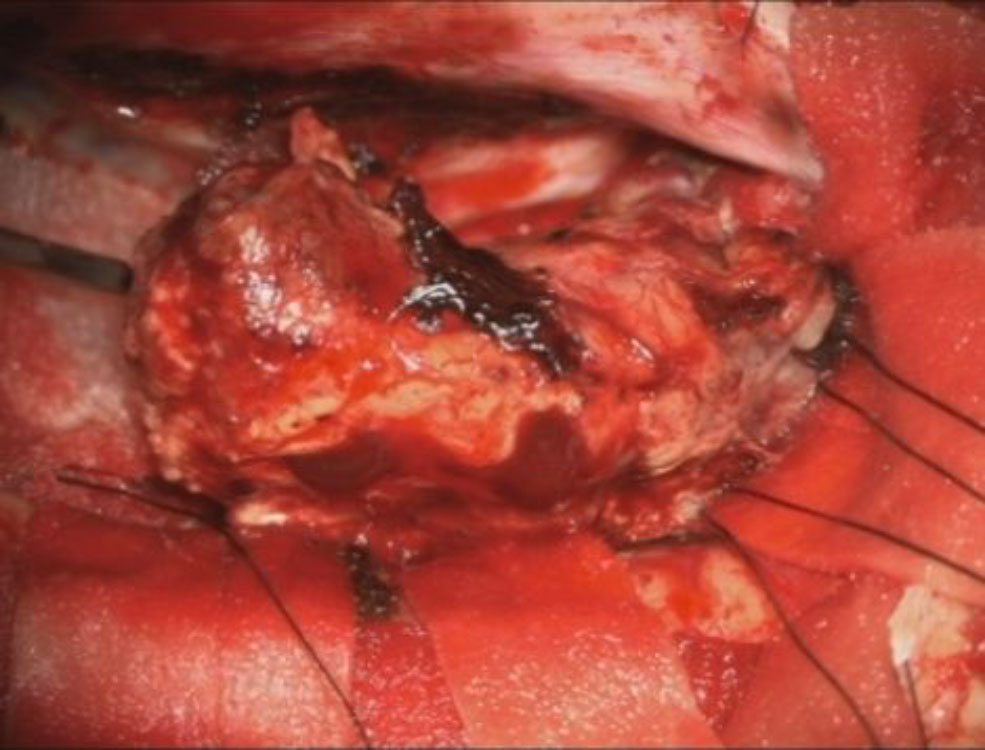

No.’25_110 摘出 前

No.’25_110  摘出 中

No.’25_110 摘出 後